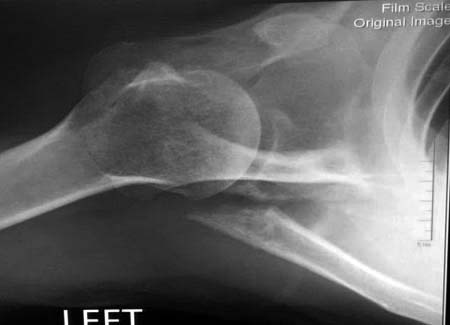

Данный перелом относится к перелому тело лопатки и несмотря на наслоение, где лопатка покрывает грудную клетку, но можно увидеть три большие фрагмента, которые находятся в разных плоскостях. Суставная поверхность расположена намного медиальнее, что нарушает бланс мышц, которая в последующем может привести к ограничению движения верхного пояса. Расположение суставной поверхности нуждается в уточнении дополнительными исследованиями, включая КТ и стандартные снимки плеча.!

Здесь пример, стандартные снимки: плечо и лопатка прямой снимок, аксиллярный и косой снимки (Y-view) и фиксация пластинами по краям, где имеется более твердая кость. Специальные пластины, хотя любая 2.7 или 3.5 мм тубулярная пластина подойдут для фиксации перелома. Риск операции - это повреждение нерва во время доступа и ре-фиксация ротаторной манжетки если потребуется широкий доступ!